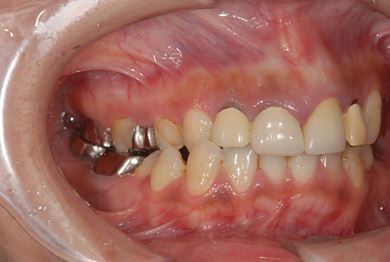

| 性別/年齢 | 女性 / 38歳 | ||||||||||||||||||||||||||||||||

| 主訴 | 奥歯の痛み(虫歯)。銀歯の所だと思います。なるべく痛くない治療がいいです。 | ||||||||||||||||||||||||||||||||

| 治療方針 | セラミック治療にて、審美的回復を行う。 | ||||||||||||||||||||||||||||||||

| 治療内容 | ハイブリッドセラミッククラウン1本(ハイブリッドセラミック用土台1本) | ||||||||||||||||||||||||||||||||

| 総治療費 | 96,600円 | ||||||||||||||||||||||||||||||||

| 治療期間 | 2ヶ月 |